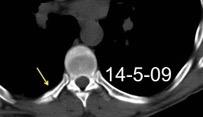

66 pacientes con

Tb pleural probada

Ocasionalmente nivel hidro-aéreo por fístula broncopleural Consolidación........3% Ganglios……….....39%

Derrame...................65-98.5%

Lesiones pleurales. ........38 %

Afect. cisura interlobar….9%

Pl. mediastínica........... 1.5%

Afect. pulmonar 26/66 … 39%

Cambios fibróticos..........17%

Cavitación ......................12%

Nódulos heterogéneos.....6%